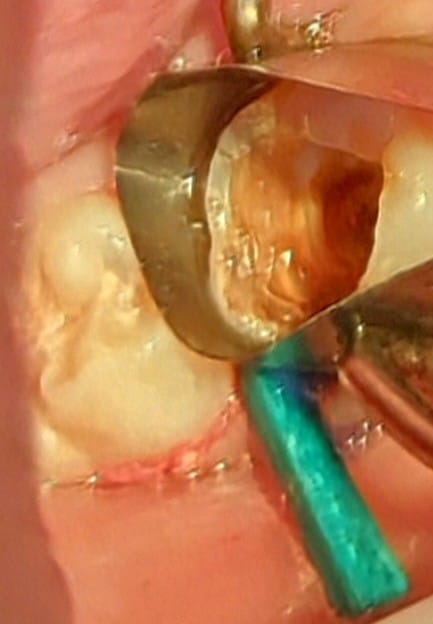

Formacresol pulpotomy till cervical constriction followed by placing calcium hydroxide as pulp capping agent for apex formation to occur naturally. sealed the tooth with temporary restoration and put the patient on 6 months follow up.